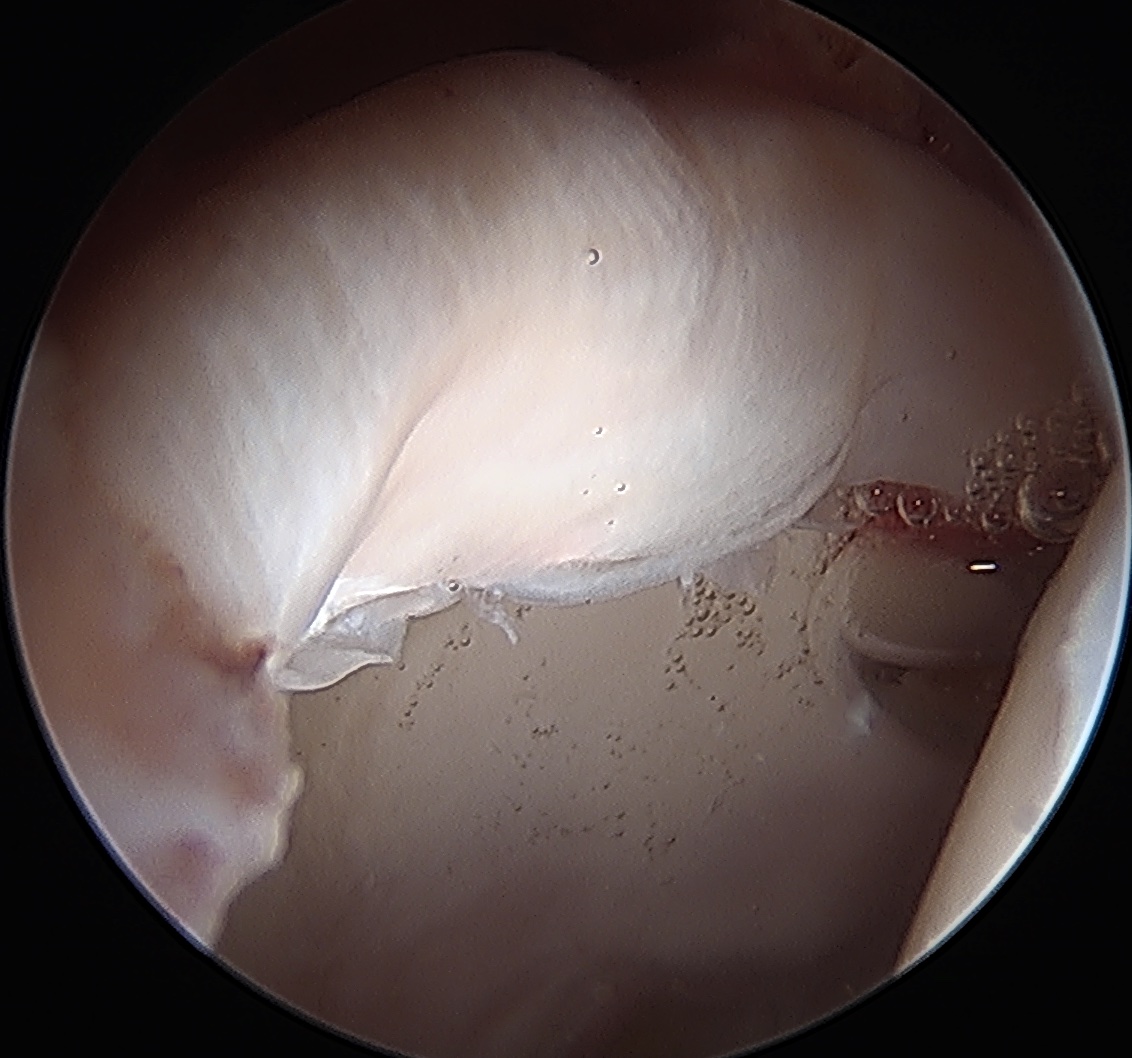

Loose bodies / trauma / synovial proliferation

Removal loose body post trauma